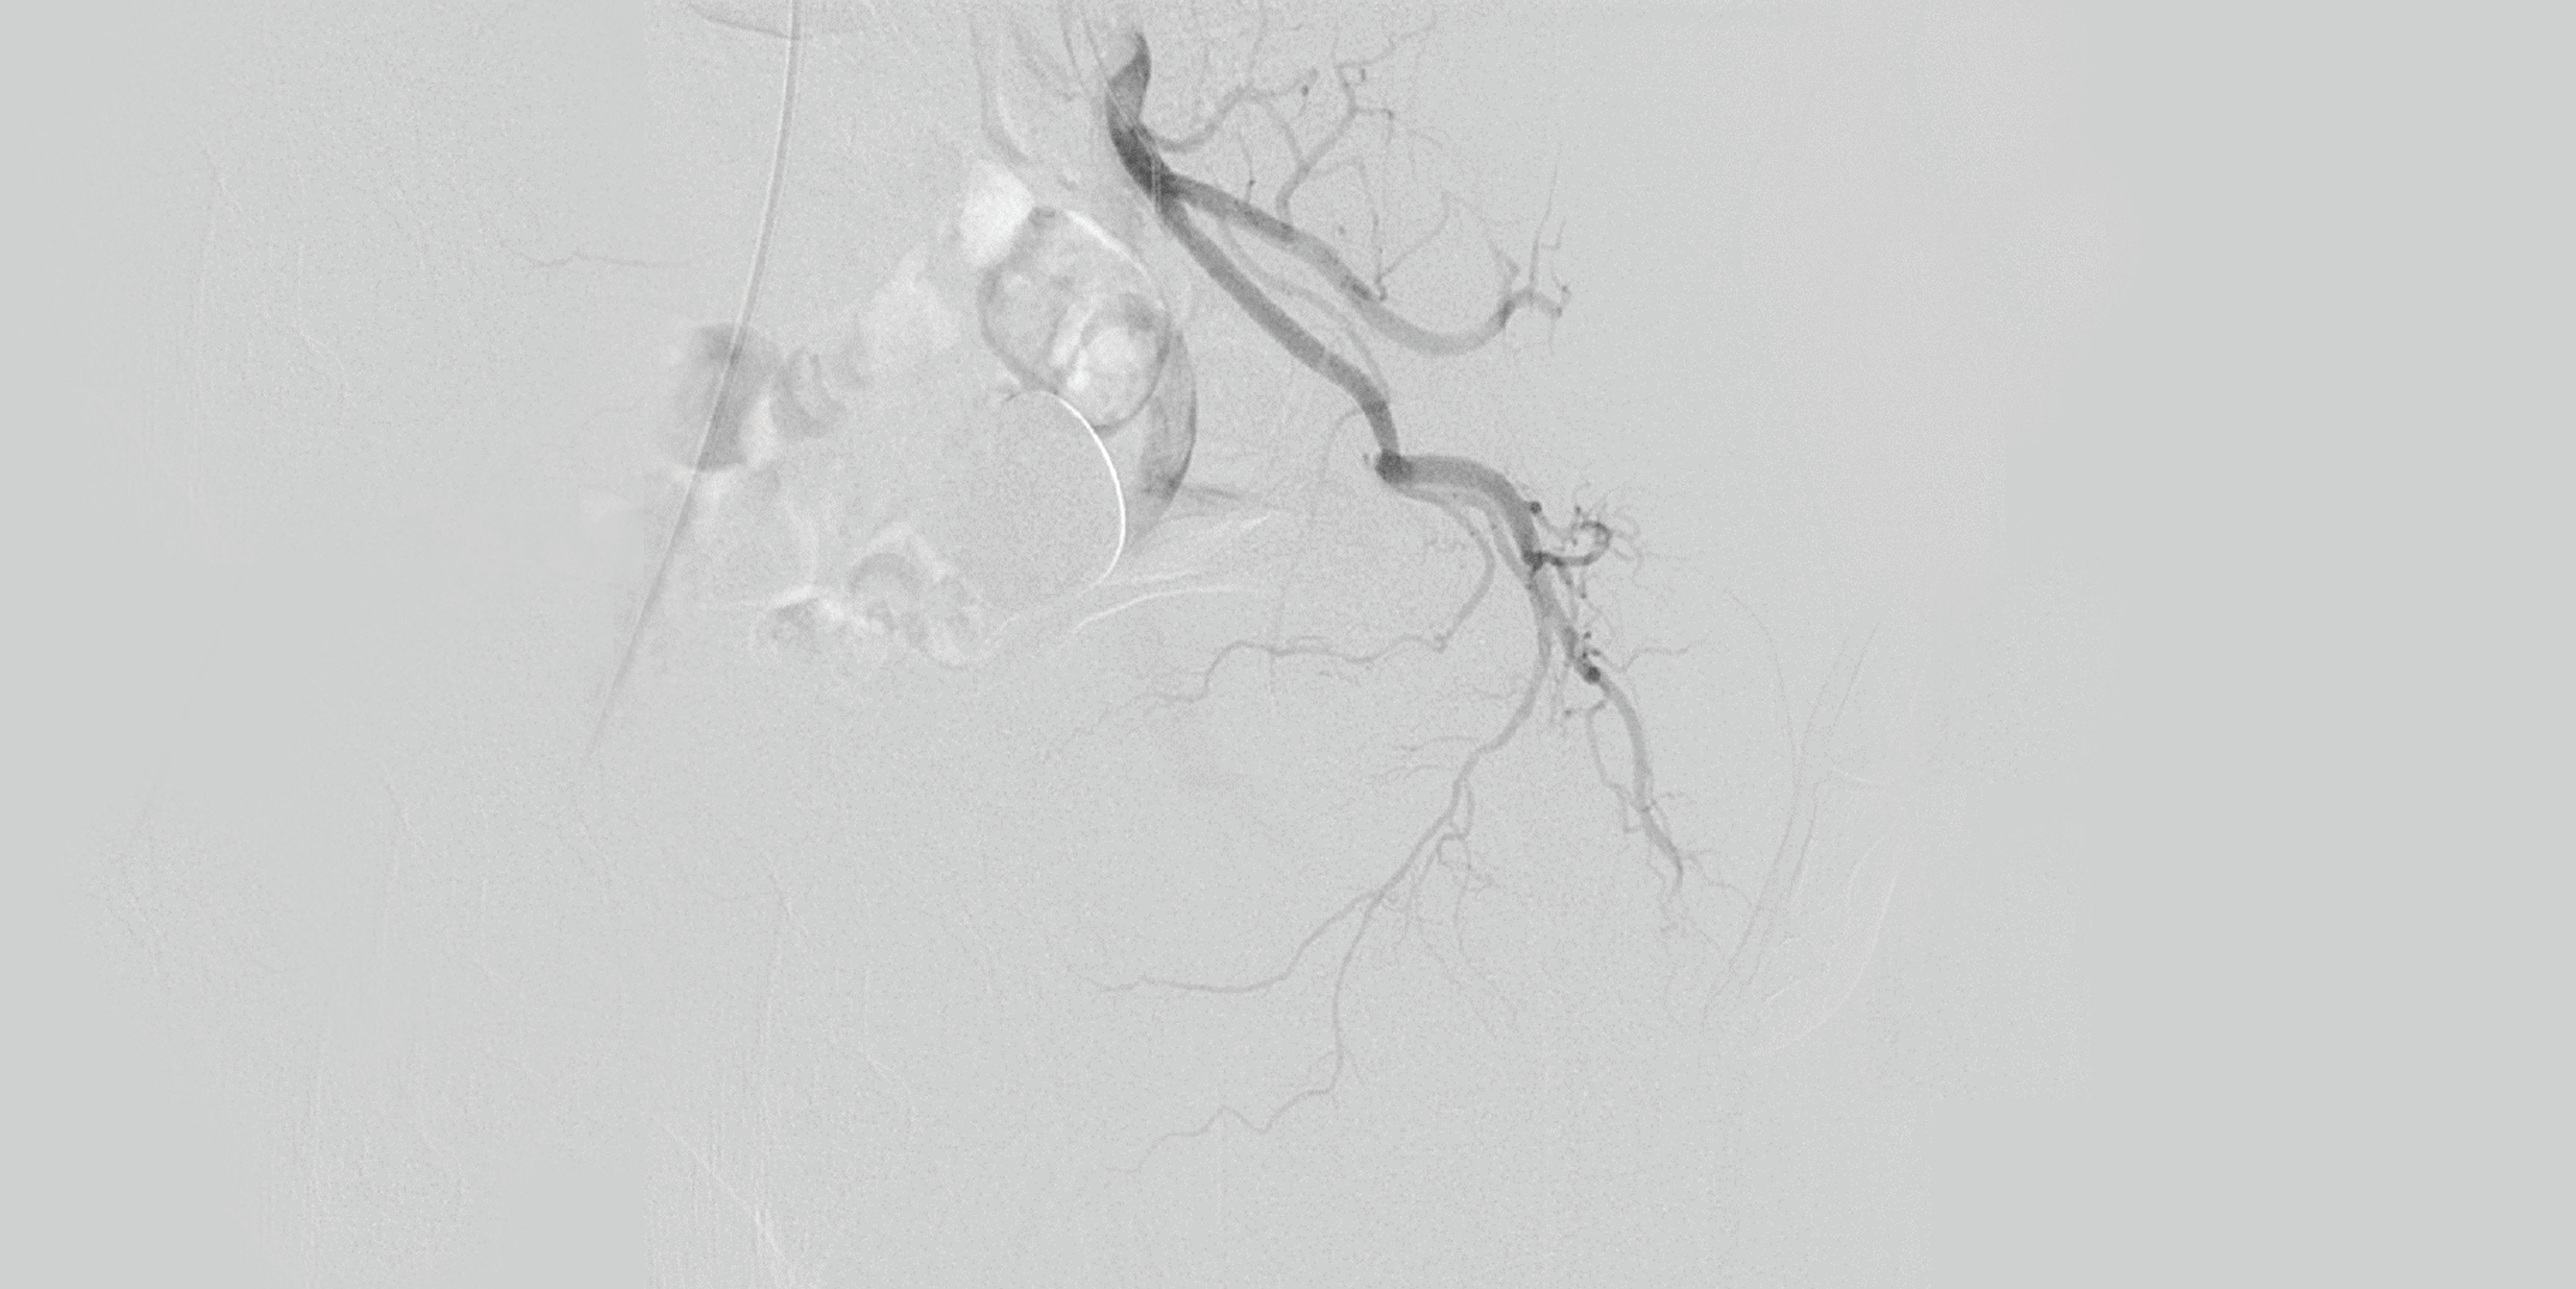

In their analysis, Powell and colleagues analysed the causes for ETF in both cohorts, the impact on major adverse limb events (MALE), above ankle amputation, death and major adverse cardiovascular events (MACE: defined as myocardial infarction, stroke and serious cardiovascular adverse events). ETF was defined as the inability to successfully complete the initial endovascular procedure.

“We approached this with an open mind,” details co-investigator John Kaufman (Oregon Health and Science University [OHSU] in Portland, USA). “We were interested that proximal SFA [superficial femoral artery]

occlusion, which was such an influential determinant, and that failure to cross the lesion was far more common than dissection, residual stenosis, or distal embolization as a failure mode.”

The investigators also analysed lesion location, which Powell highlights as a strength of their trial. In determining this, he hopes that granular predictions can be developed for patients that are less likely to achieve technical success, to map potential failure modes for each specific case.